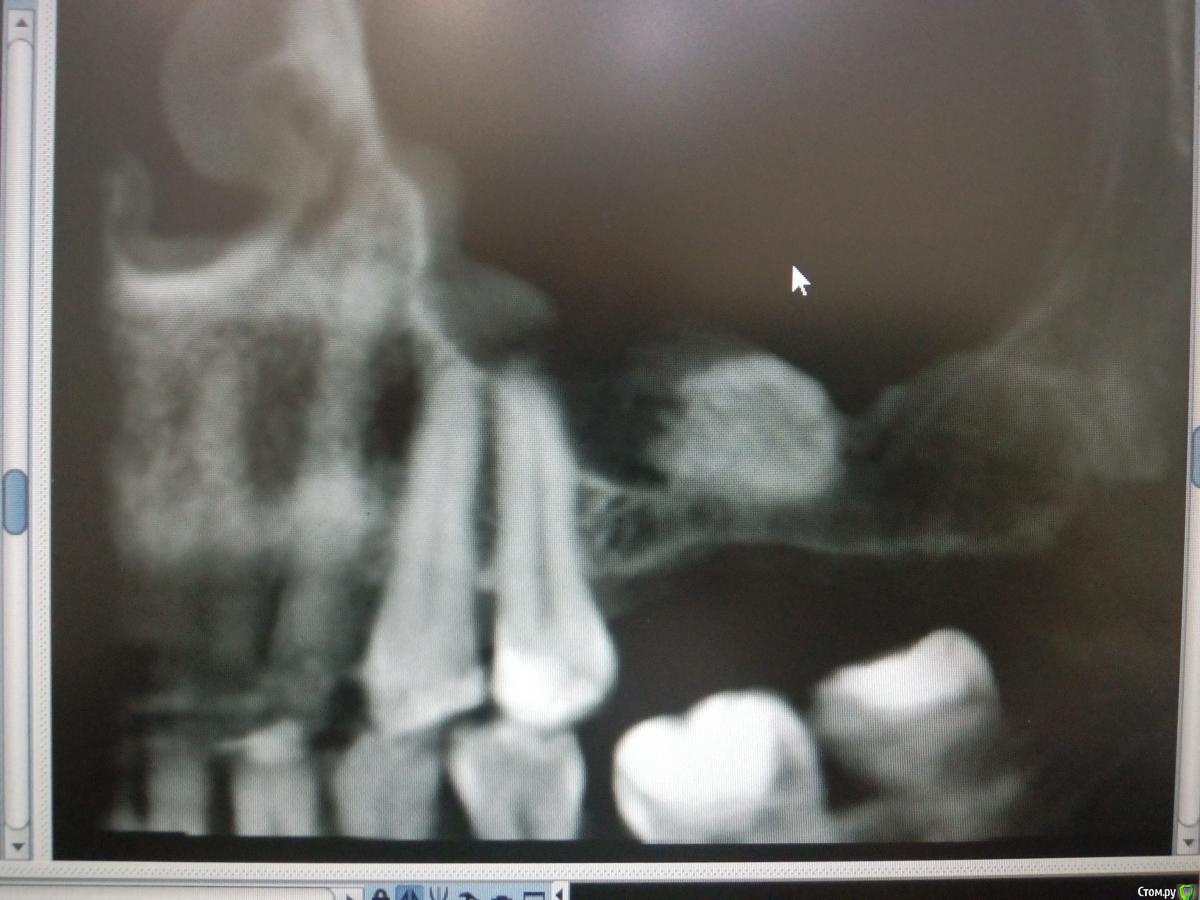

Sampson Опубликовано 14 августа, 2018 Поделиться Опубликовано 14 августа, 2018 (изменено) В феврале провел первый свой открытый синус.Снимок доПосле операцииНеделю назад пришла на контроль. Изменено 14 августа, 2018 пользователем Sampson Ссылка на комментарий

колесников Опубликовано 14 августа, 2018 Поделиться Опубликовано 14 августа, 2018 (изменено) То что вы отслоились небной-это превосходно! Обычно,по началу,многие побаиваются углубляться и дальше окна не ходят. Но я бы рекомендовал ещё мезиодистально отслаиваться. Теперь спереди и сзади от графита ямы для скапливания слизи ,причина пролиферации шнейдеровой. Изменено 14 августа, 2018 пользователем колесников 2 Ссылка на комментарий

Bier Опубликовано 14 августа, 2018 Поделиться Опубликовано 14 августа, 2018 согласен с Колесниковым, медиально надо было шире значительно. Теперь даже позиция имплантата не очень то выходит.. В натяг попадаете в медиальный край аугментата. Ссылка на комментарий

pit Опубликовано 14 августа, 2018 Поделиться Опубликовано 14 августа, 2018 Из этого случая надо просто сделать вывод и впредь делать доступ медиальнее и протяженнее. Или 2 окна. В данном случае я бы установил имплантаты в центр аугментата и в позицию "полвосьмого" зуба и сделал бы 3 коронки. 26 зуб - консольная единица, отмоделировал как премоляр. Лучшее объяснение больному, на вопрос: "почему 3 коронки?" - в необходимой позиции не выросла костная ткань, поэтому имплант ставится дальше от 25 зуба и если делать 2 коронки, как запланировано, то постоянно будет забиваться пища и это будет невыносимо противно) 1 Ссылка на комментарий